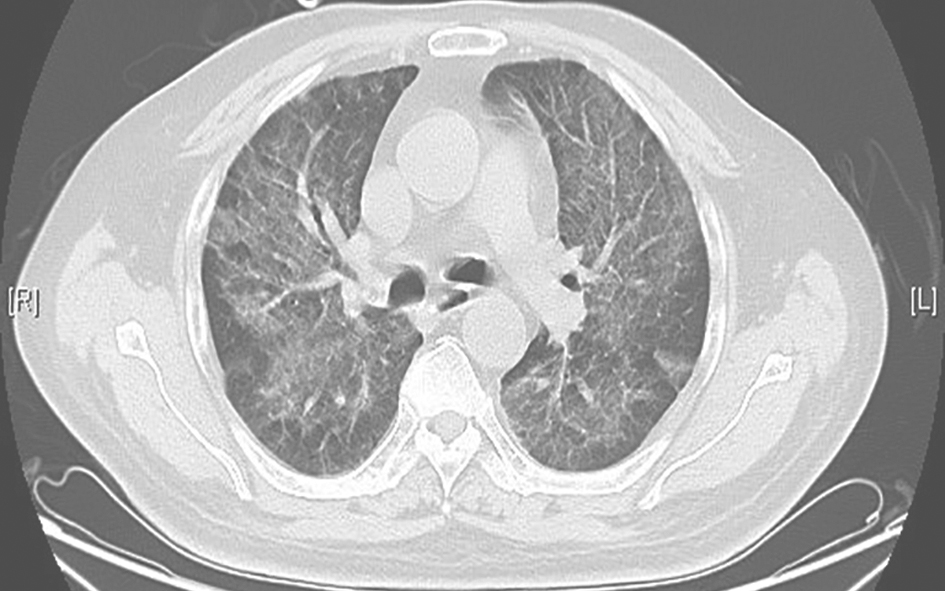

胸部CT:入院前3个月胸部CT示双肺弥漫性间质病变,可见磨玻璃和斑片高密度影,伴部分间质纤维化(图1)。予激素、抗感染及对症治疗后复查胸部CT,见双肺间质性病变较前增多。

图1胸部CT表现(2013-02-02)

发病初期,胸部CT见双肺间质弥漫性磨玻璃样渗出伴斑片高密度影,累及叶间裂